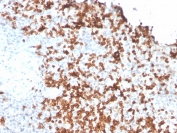

IHC staining of FFPE human spleen with Granzyme B antibody (clone GZMB/3056). HIER: boil tissue sections in pH 9 10mM Tris with 1mM EDTA for 10-20 min and allow to cool before testing.